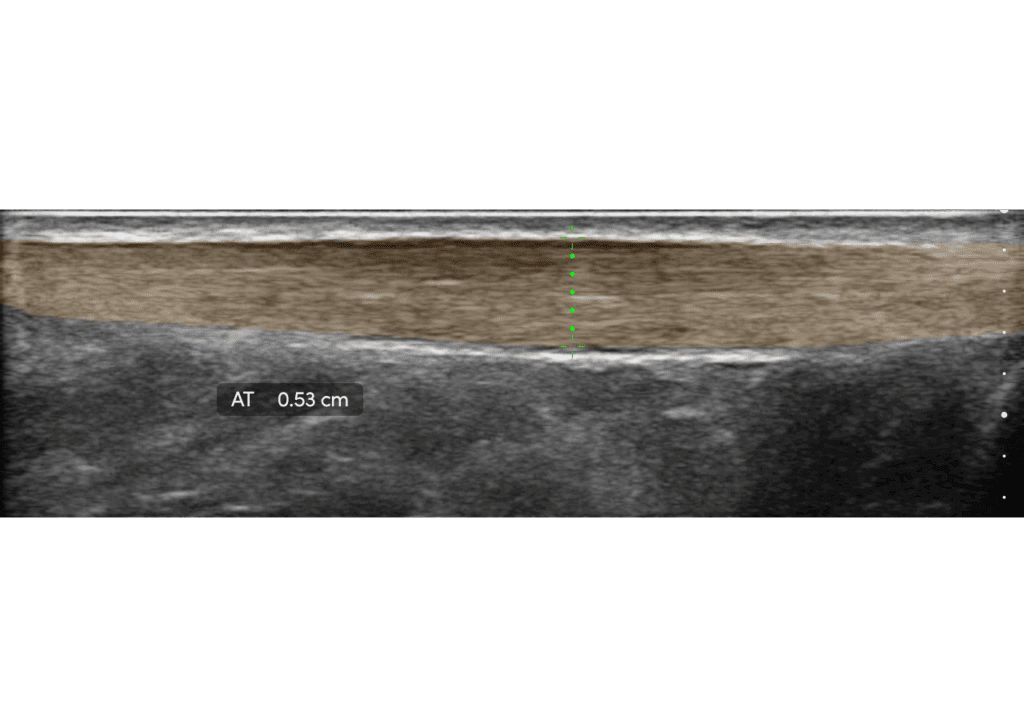

The Clarius L15 HD3 is the perfect probe for sports medicine.